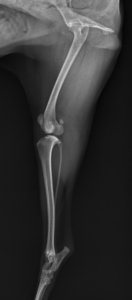

主な検査はレントゲン検査です。骨折部位や骨片のズレ、粉砕の程度を評価します。必要に応じて以下の検査が行われます。

・複数方向からのレントゲン

骨折の治療方法

・外固定(ギプス、包帯)

・内固定(プレート、ピン、スクリュー)

・創外固定

軽度の骨折では外固定のみで治癒することもありますが、多くの場合、安定した治癒を目指して手術が選択されます。